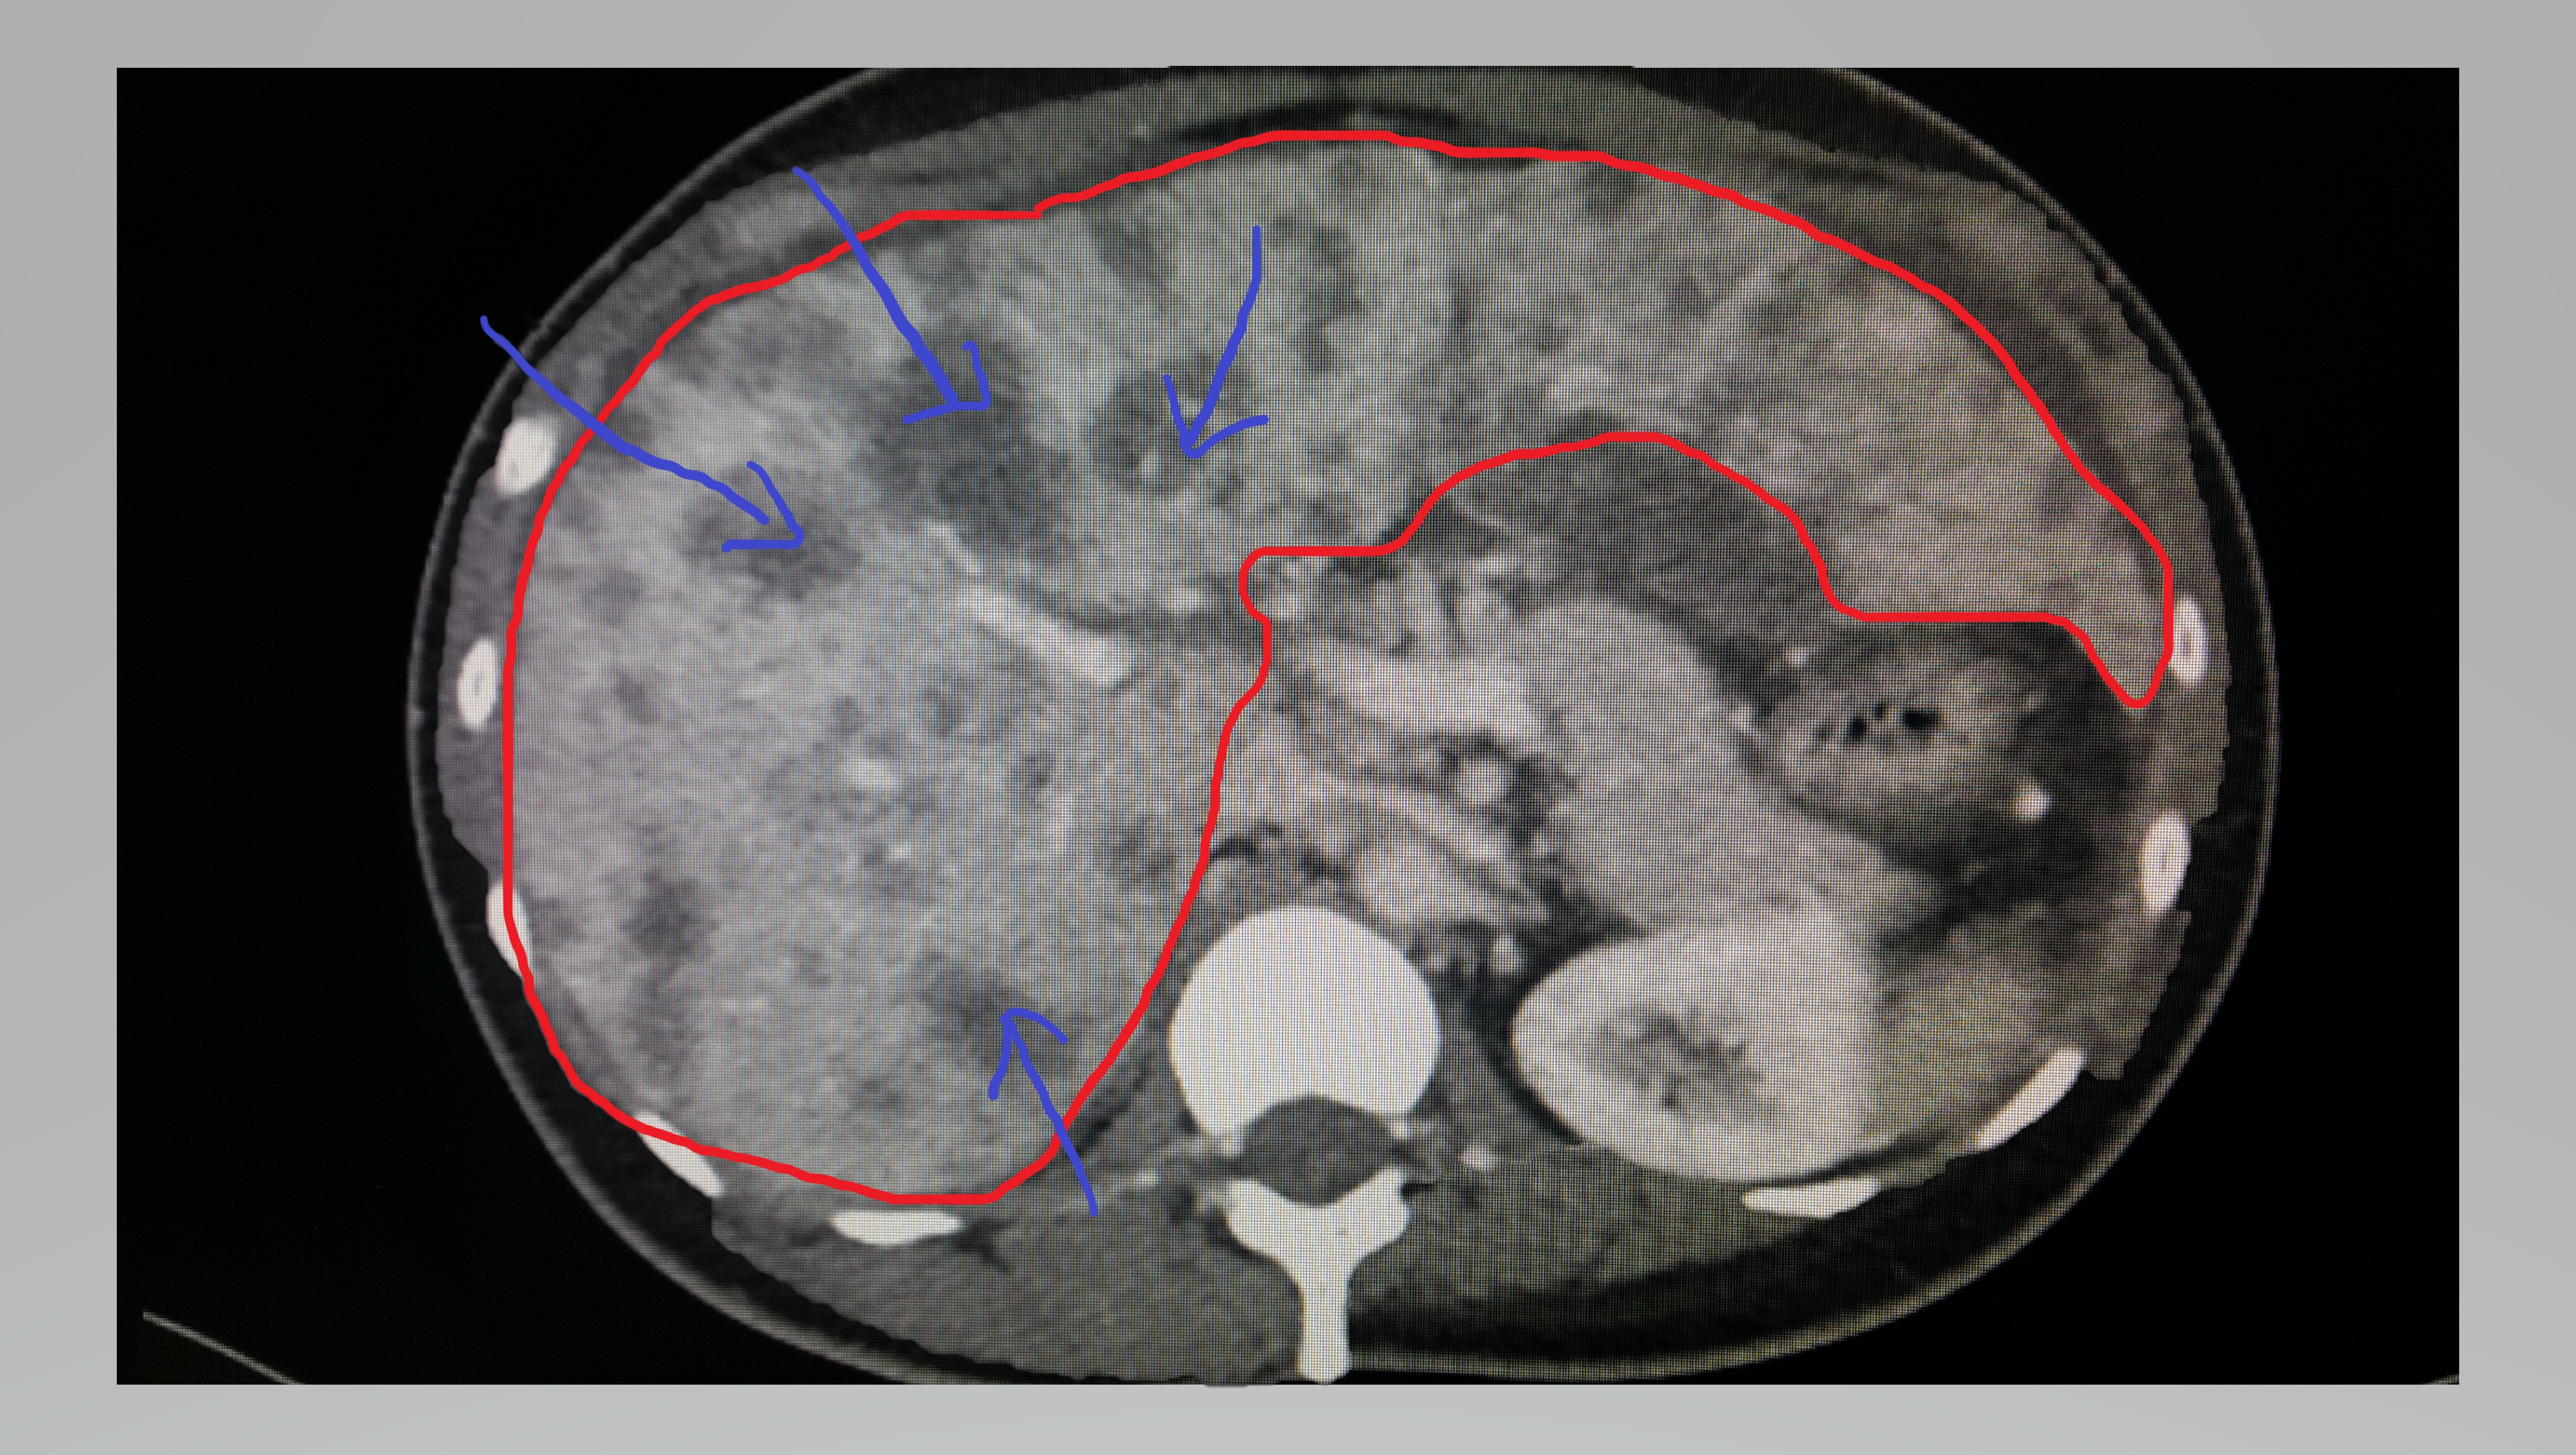

빨간색 테두리가 간이다. 파란색 화살표가 전이된 암이다. 간에 빼곡하게 전이된 암이 보인다.